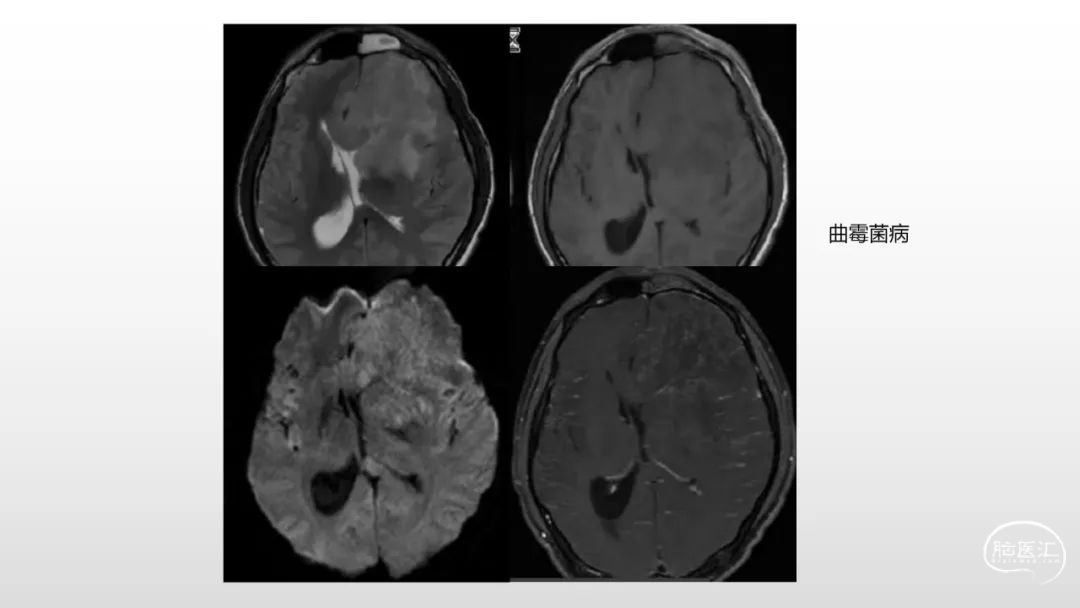

颅脑影像诊断基础知识讲座:感染和免疫性疾病1